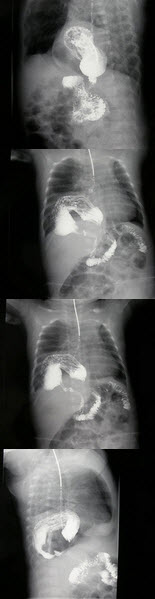

258、单项选择题

女,1岁,反复呕吐伴中度营养不良,结合影像,最可能的诊断为()

A.肺脓疡

B.膈疝

C.食道裂孔疝

D.包裹性液气胸

E.胃扭转